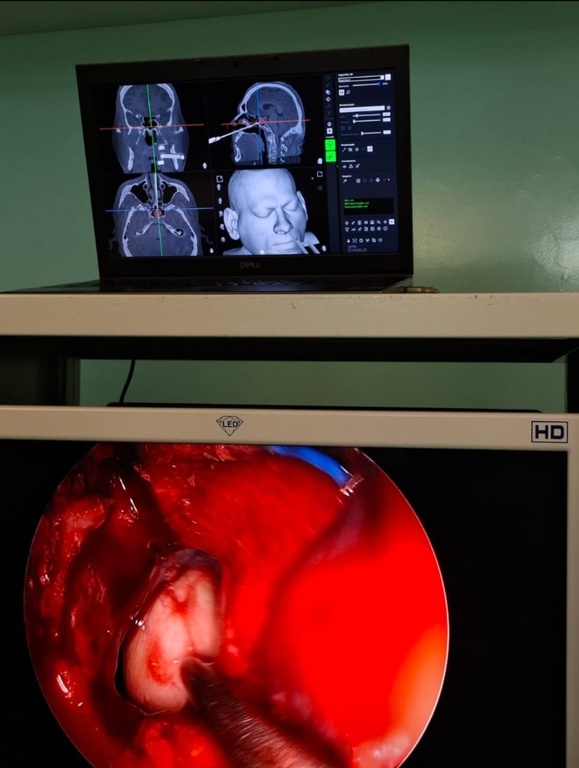

O procedimento de alta complexidade conta com a atuação conjunta das especialidades de neurocirurgia e otorrinolaringologia. A cirurgia da base do crânio foi realizada por meio das fossas nasais, sem a necessidade de cortes externos. O método minimamente invasivo associou técnicas endoscópicas à navegação em tempo real, proporcionando mais segurança e precisão.

O neurocirurgião Marcus Vinícius Oliveira dos Santos explica que o sistema de neuronavegação é semelhante a um “GPS cirúrgico”, permitindo ao médico visualizar, em tempo real, a posição da lesão com base em imagens de tomografia e ressonância magnética. “A incorporação da tecnologia ao procedimento cirúrgico aumenta a segurança do ato e permite ressecções mais amplas, com menor risco de complicações”, afirma o especialista.

A participação da otorrinolaringologia foi essencial no procedimento. O médico Danilo de Negreiros Freitas foi responsável pelo acesso cirúrgico por via nasal, utilizando técnicas endoscópicas para alcançar áreas complexas da base do crânio. “A experiência do otorrinolaringologista em cirurgia endoscópica permite uma manipulação precisa dos instrumentos e câmeras, auxiliando o neurocirurgião durante toda a cirurgia. A presença de dois cirurgiões também facilita a manutenção do campo operatório, especialmente em situações mais delicadas ou que exigem diferentes ângulos de visão”, destaca.

O procedimento envolveu o uso de endoscópios acoplados a câmeras, que transmitem imagens em tempo real para um monitor de vídeo, dispensando incisões na face ou no crânio. Instrumentais cirúrgicos delicados foram utilizados em todas as etapas: desde a exposição da área até a remoção do tumor e o fechamento com retalhos, enxertos, materiais sintéticos e cola biológica. “A neuronavegação nos permite trabalhar com maior segurança e precisão, reduzindo riscos e otimizando os resultados para o paciente”, finaliza Danilo de Negreiros Freitas.